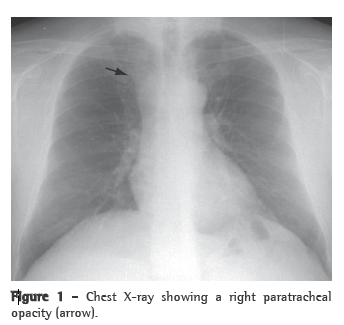

A 50-year-old male smoker (30 pack-years), a car salesman with a history of arterial hypertension and dyslipidemia, sought medical attention. The patient was under regular treatment with simvastatin (20 mg), valsartan (80 mg), lansoprazole (30 mg), and brotizolam (0.25 mg). The patient was referred to a pulmonologist due to the finding of right paratracheal lesion with enlargement of the upper mediastinum on a routine chest X-ray (Figure 1).

The presumed diagnosis is made based on the detection of a cystic lesion on a chest X-ray or a computed tomography scan of the chest.(5) On X-rays, lymphangiomas of the mediastinum appear as well-circumscribed, round masses of homogeneous density,(5) and computed tomography of the chest demonstrates the involvement or deviation of natural structures, absence of calcification, and various high attenuation areas within the lesion.(2)